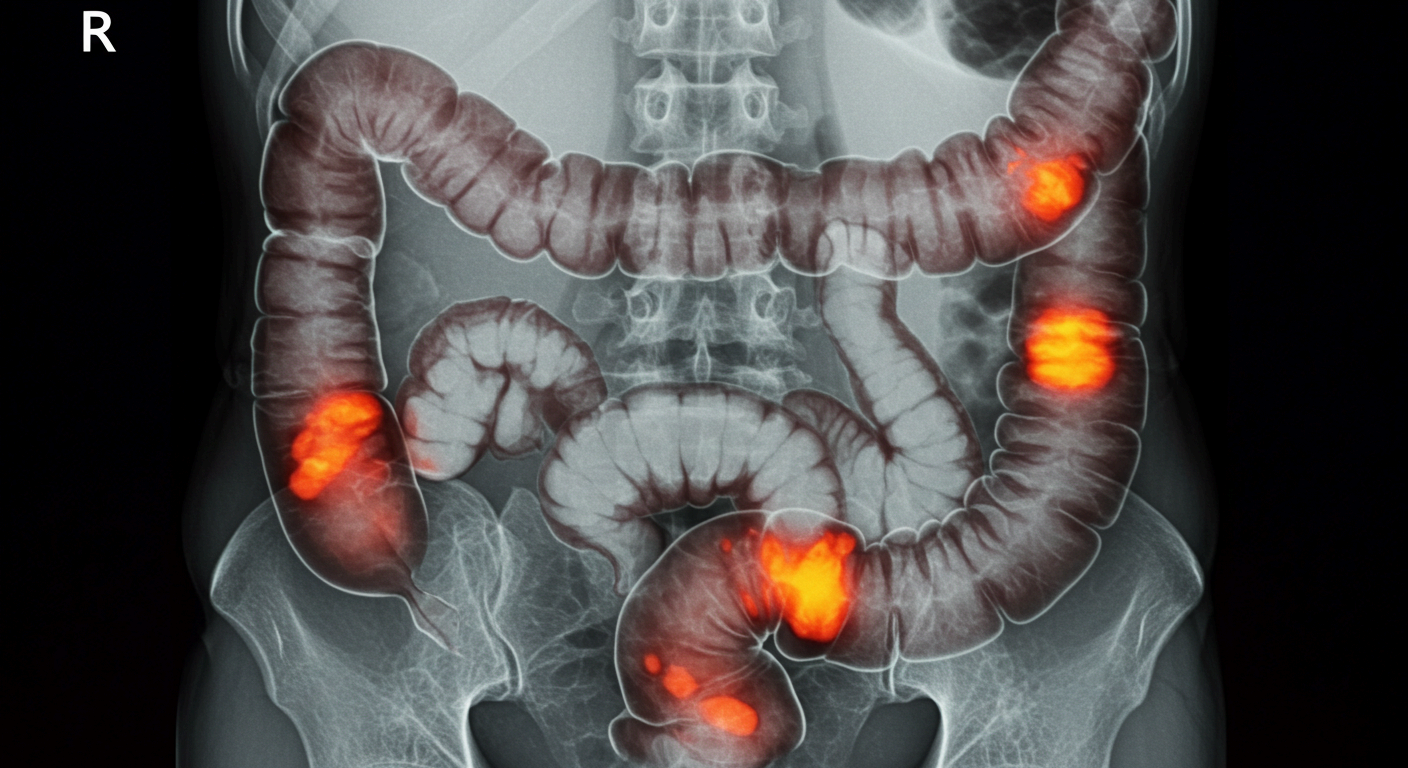

2. 병원 치료 방법

장폐색 증상이 나타났을 때는 자가 치료보다 신속한 병원 치료가 최우선입니다.

• 수술적 치료

종양, 탈장, 장중첩증, 혈류 차단 등이 원인일 경우에는 수술이 불가피합니다. 장을 절제하거나 유착을 풀어주는 수술을 통해 근본적인 문제를 해결합니다.